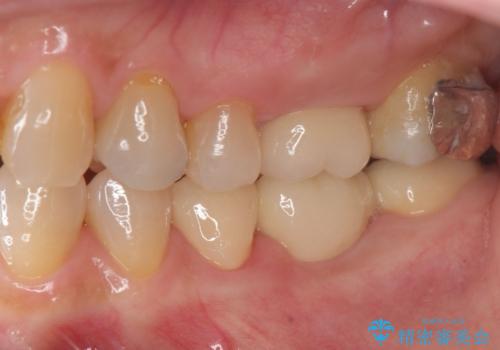

抜歯後の補綴 セラミックブリッジ治療

- 他院で行われた抜歯後の機能回復について相談に来院されました。

インプラント治療、入れ歯と比較し、前後の銀歯や詰め物の問題も一緒に治療のできるブリッジ治療を選択されました。

ブリッジは早期に審美性・機能性を回復できる治療法です。

- 39.6万円(ジルコニアクラウン×3・仮歯×3)費用は治療当時の料金となります

前後の歯も一緒に審美性を回復することができ、喜んでいただくことができました。